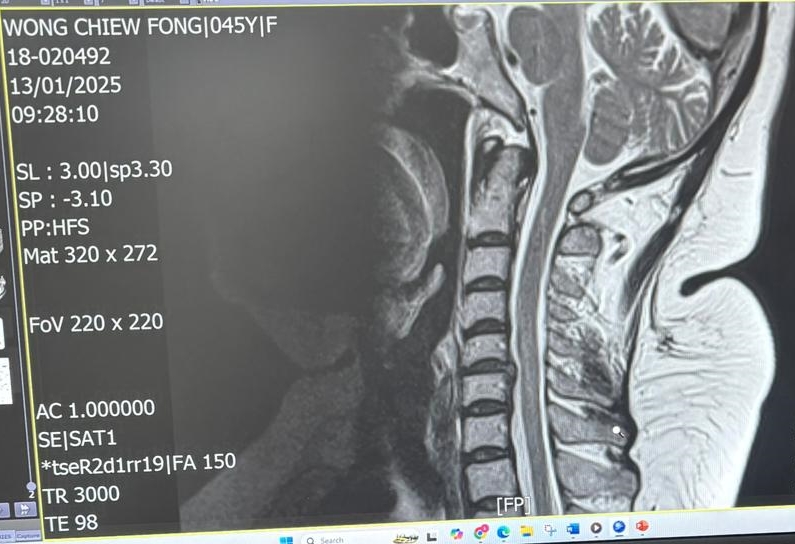

然而,去年6月一次跌倒意外后,她的双手开始麻痹,症状迅速恶化。今年1月的MRI报告证实,她的脑部出现血块,而C5&C6颈椎间盘严重突出,压迫神经线。

惟医生亦建议尽快进行颈椎间盘切除及融合手术(ACDF),否则麻痹可能进一步恶化,甚至影响手部功能与日后行动能力。